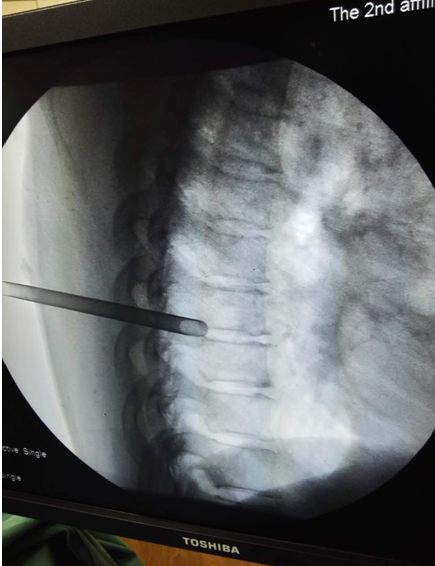

术前定位2

(术前定位2